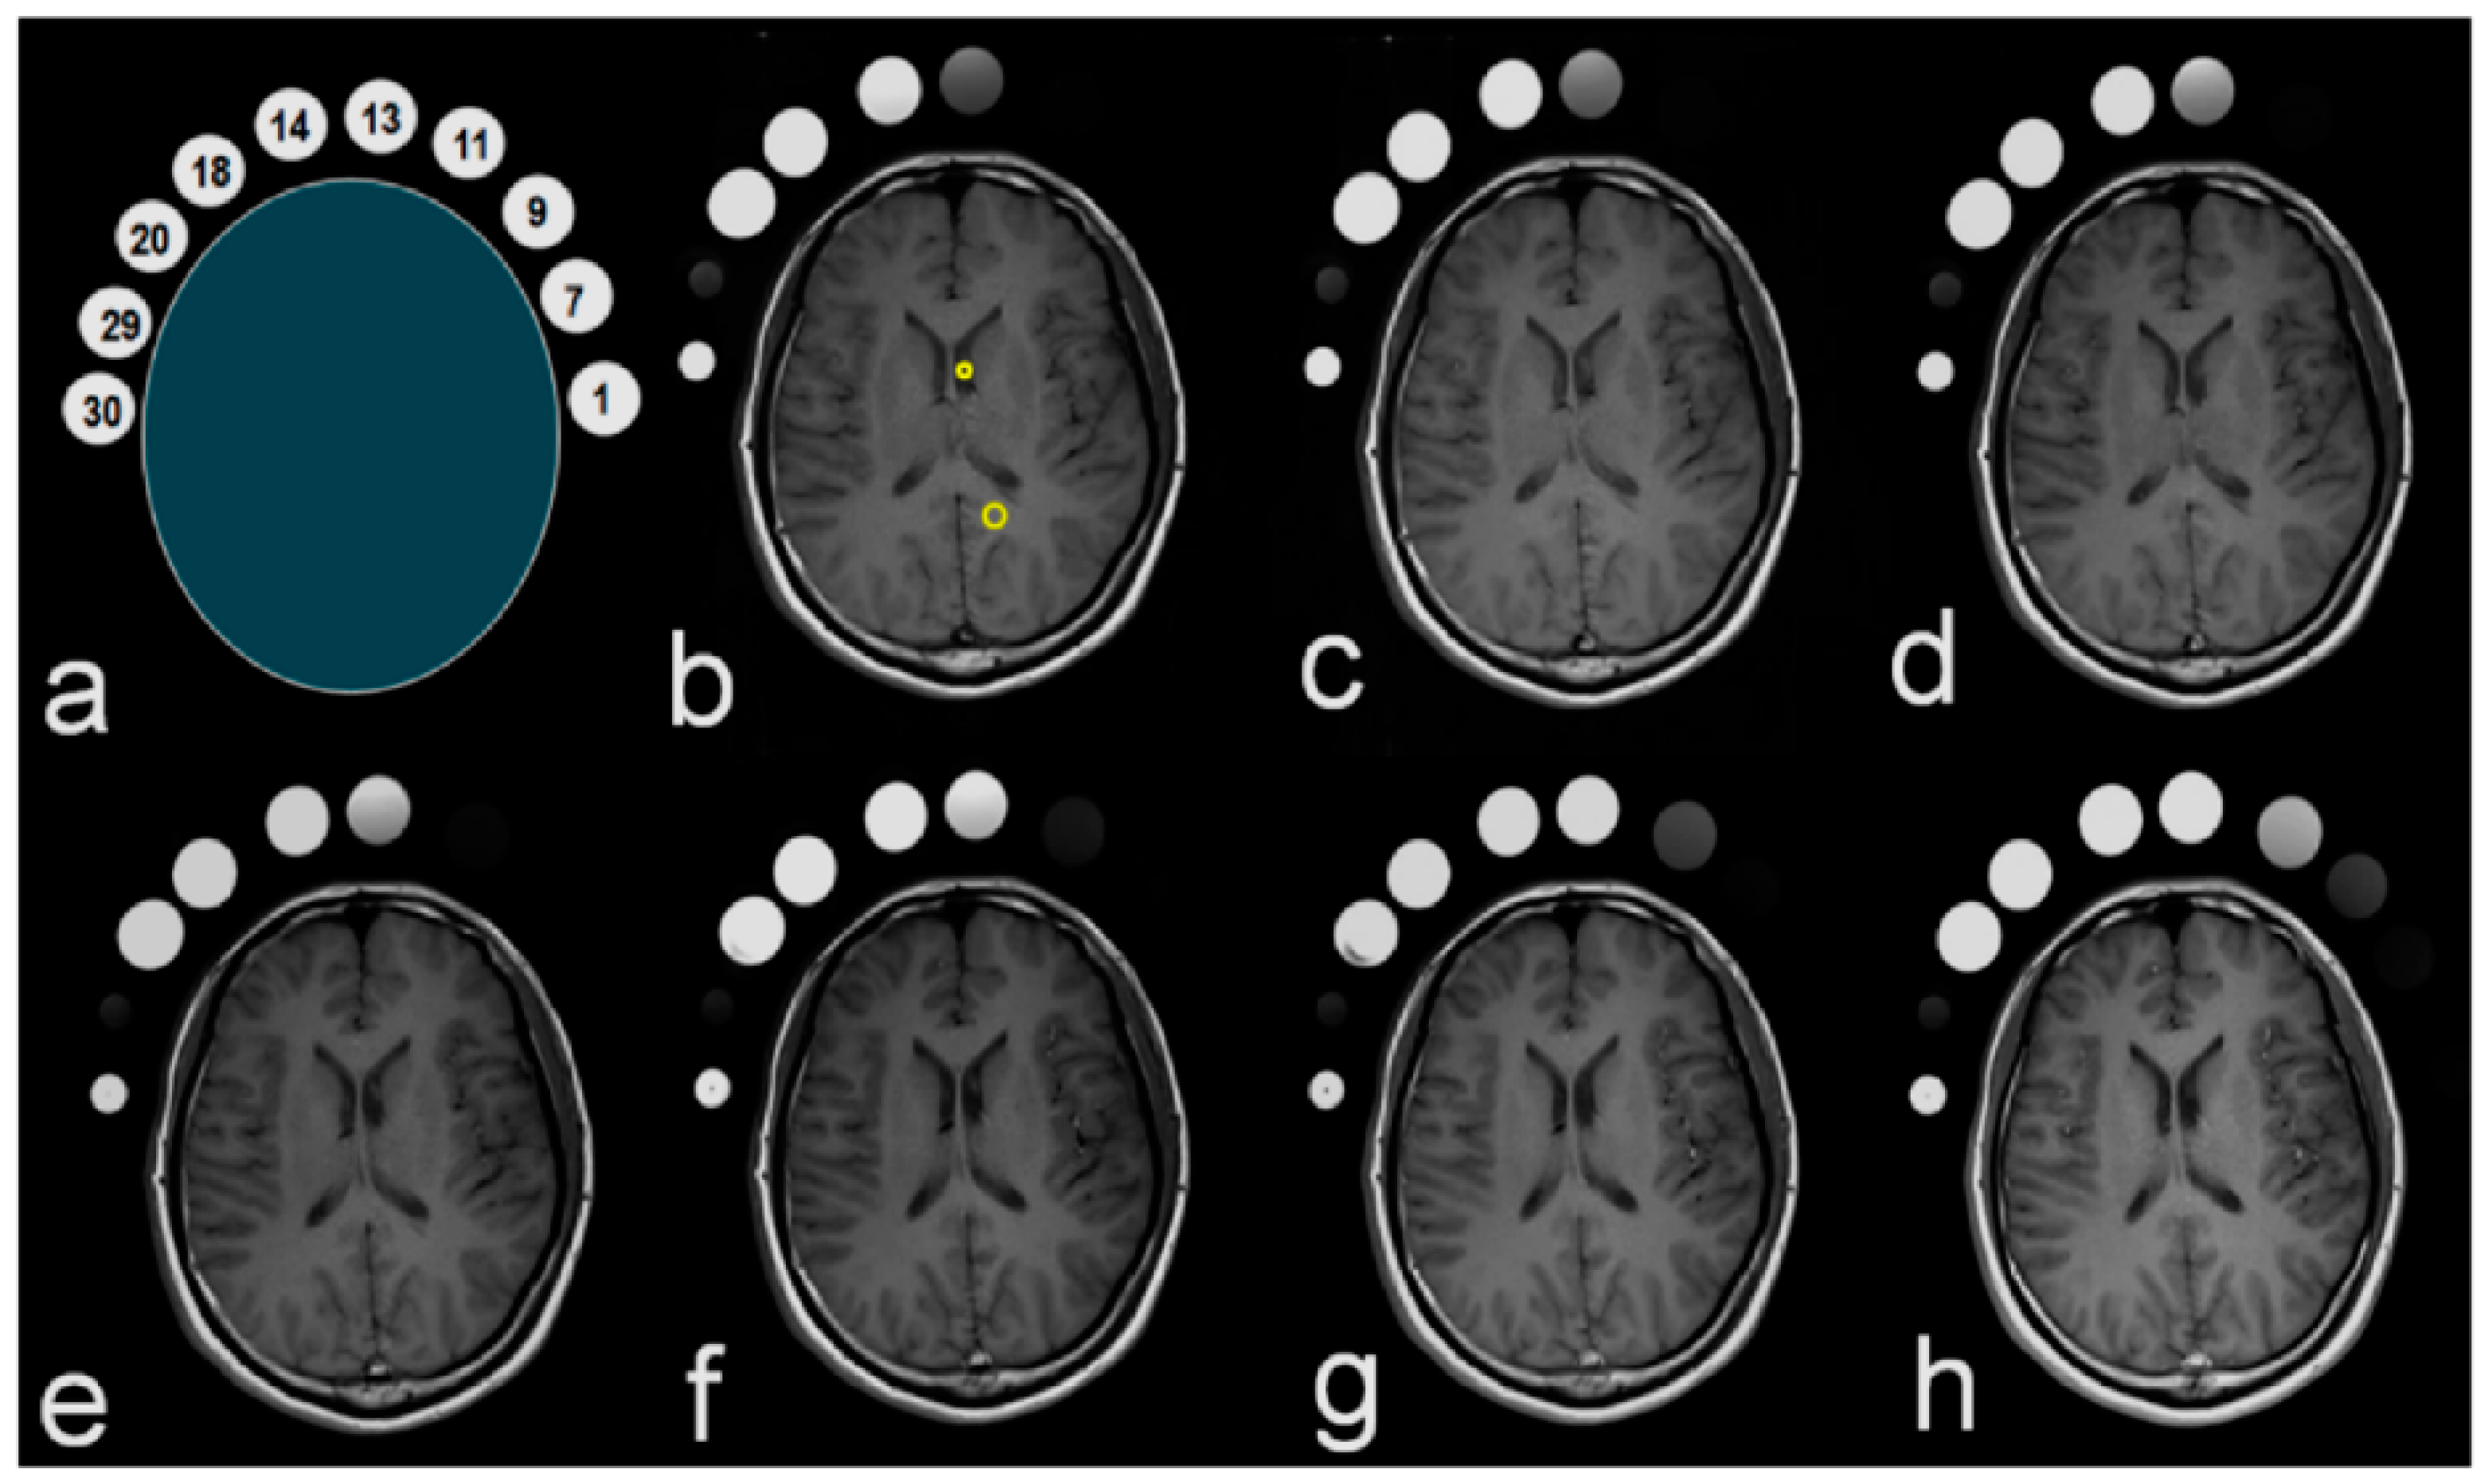

3.3. Clinical Study

Figure 6 shows images from the clinical study. The SI of the brain parenchyma and clinical phantom were compared with varying TEs. To this end, the SI was measured in the clinical phantom and in selected ROIs within the CSF and the brain parenchyma, as shown in Figure 6. According to the statistical analyses, there was not a significant difference between SSI2 and SC. Table 4 shows the SSI2, FSI2, SC, SBP, ASTM, EPSS, SEPSS, EPSC, and AEPSC for different TEs. As TE was decreased from 25 to 7 msec, SSI2 and SC did not show a significant change, while FSI2, SBP, and ASTM showed increasing patterns from 804 to 1106, 278 to 389, and 378 to 845 a.u., respectively. EPSS and EPSC were calculated as shown in Table 4; the respective averages for these values, AEPSS and AEPSC, both increased with shorter TE, from 47.0 to 140.3% and from 224.3 to 647.8%, respectively. The correlation coefficients were calculated to determine the associations between TE change and the contrast values for EPSS and EPSC, which presented significant negative correlations for most values.

Figure 6.

Images of the clinical study. (a) container numbers for the clinical phantom; (b) changes in SI for a 25 msec TE; (c) changes in SI for a 22 msec TE; (d) changes in SI for a 19 msec TE; (e) changes in SI for a 16 msec TE; (f) changes in SI for a 13 msec TE; (g) changes in SI for a 10 msec TE; (h) changes in SI for a 7 msec TE. SI, signal intensity; TE, echo time.

We also conducted a clinical study for direct comparisons with brain images, and obtained the following results. First, as seen in Figure 6, the GBCA signal enhancement at low concentrations was visibly increased in the clinical phantom as TE was decreased. Indeed, the ASTM graph in Figure 7a demonstrates increasing SI with decreasing TE. In order to compare the free water SI of saline in the clinical phantom and CSF in the body, we produced the graph in Figure 7b. Little difference was observed between the values at all TEs, with both measures varying in the range 120–130 a.u. In other words, the SI in free water was similar in the clinical phantom to that in the body. The SI in the brain parenchyma was higher than in free water, as shown by the SBP in Figure 7b, and FSI2 was even higher than SBP. Here, SBP and FSI2, with a constant molecular weight, showed an increase in signal with decreasing TE, whereas there was little change in the CSF signal.